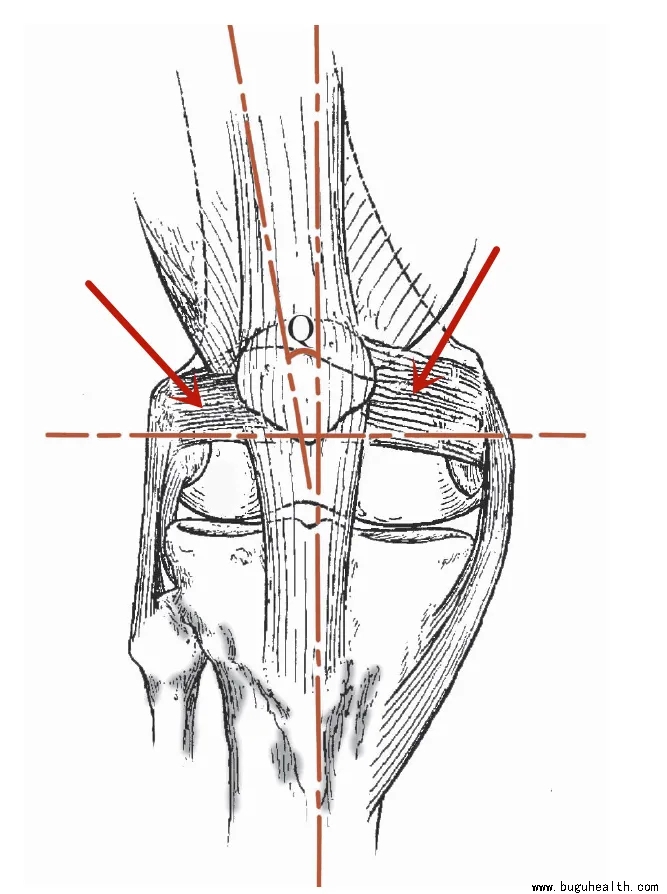

- 布骨医学科普:浅谈髌骨脱位 布骨康复医疗中心 ,2021-12-01

- 有报道显示,髌骨脱位的发病率可达0.042%,其中10~17岁的女性发病风险最高,可达0.108%,患膝复发率为22.7%。如髌骨脱位处理不当,将不同程度地加快膝关节的退变,严重影响患者的生活质量,并在日后给患者带来沉重的心理负担。.....